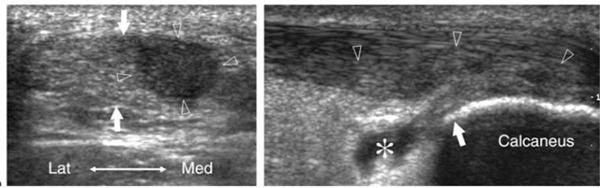

윗 사진은 종골(발뒤꿈치뼈) 위쪽의 아킬레스 건의 초음파 영상으로 좌측은 단축으로. 우측은 장축으로 찍은 영상이다. 좌측에 보면 가운데에 빈 구멍이 보이는데 이 부위는 아킬레스건이 외부적 충격으로 끊어진 것이 아니라 단순 퇴행성 변화로 힘줄이 연하게 된 부위이다. 힘줄의 상태변화에 의해서 초음파를 덜 반사하는 구간이 만들어진 것이다.